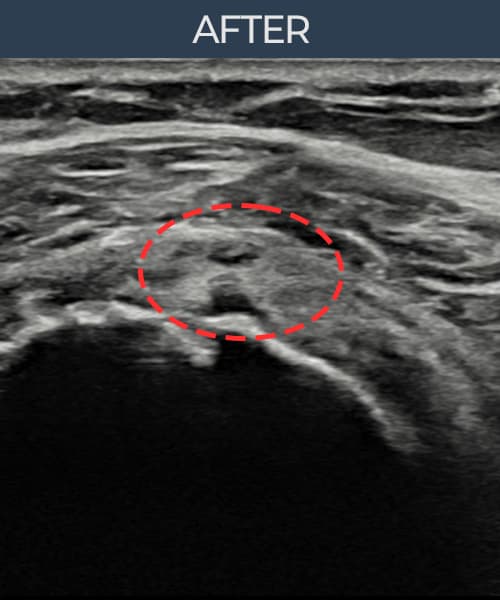

左侧 冈上肌腱 石灰化肌腱炎

9mm × 7mm